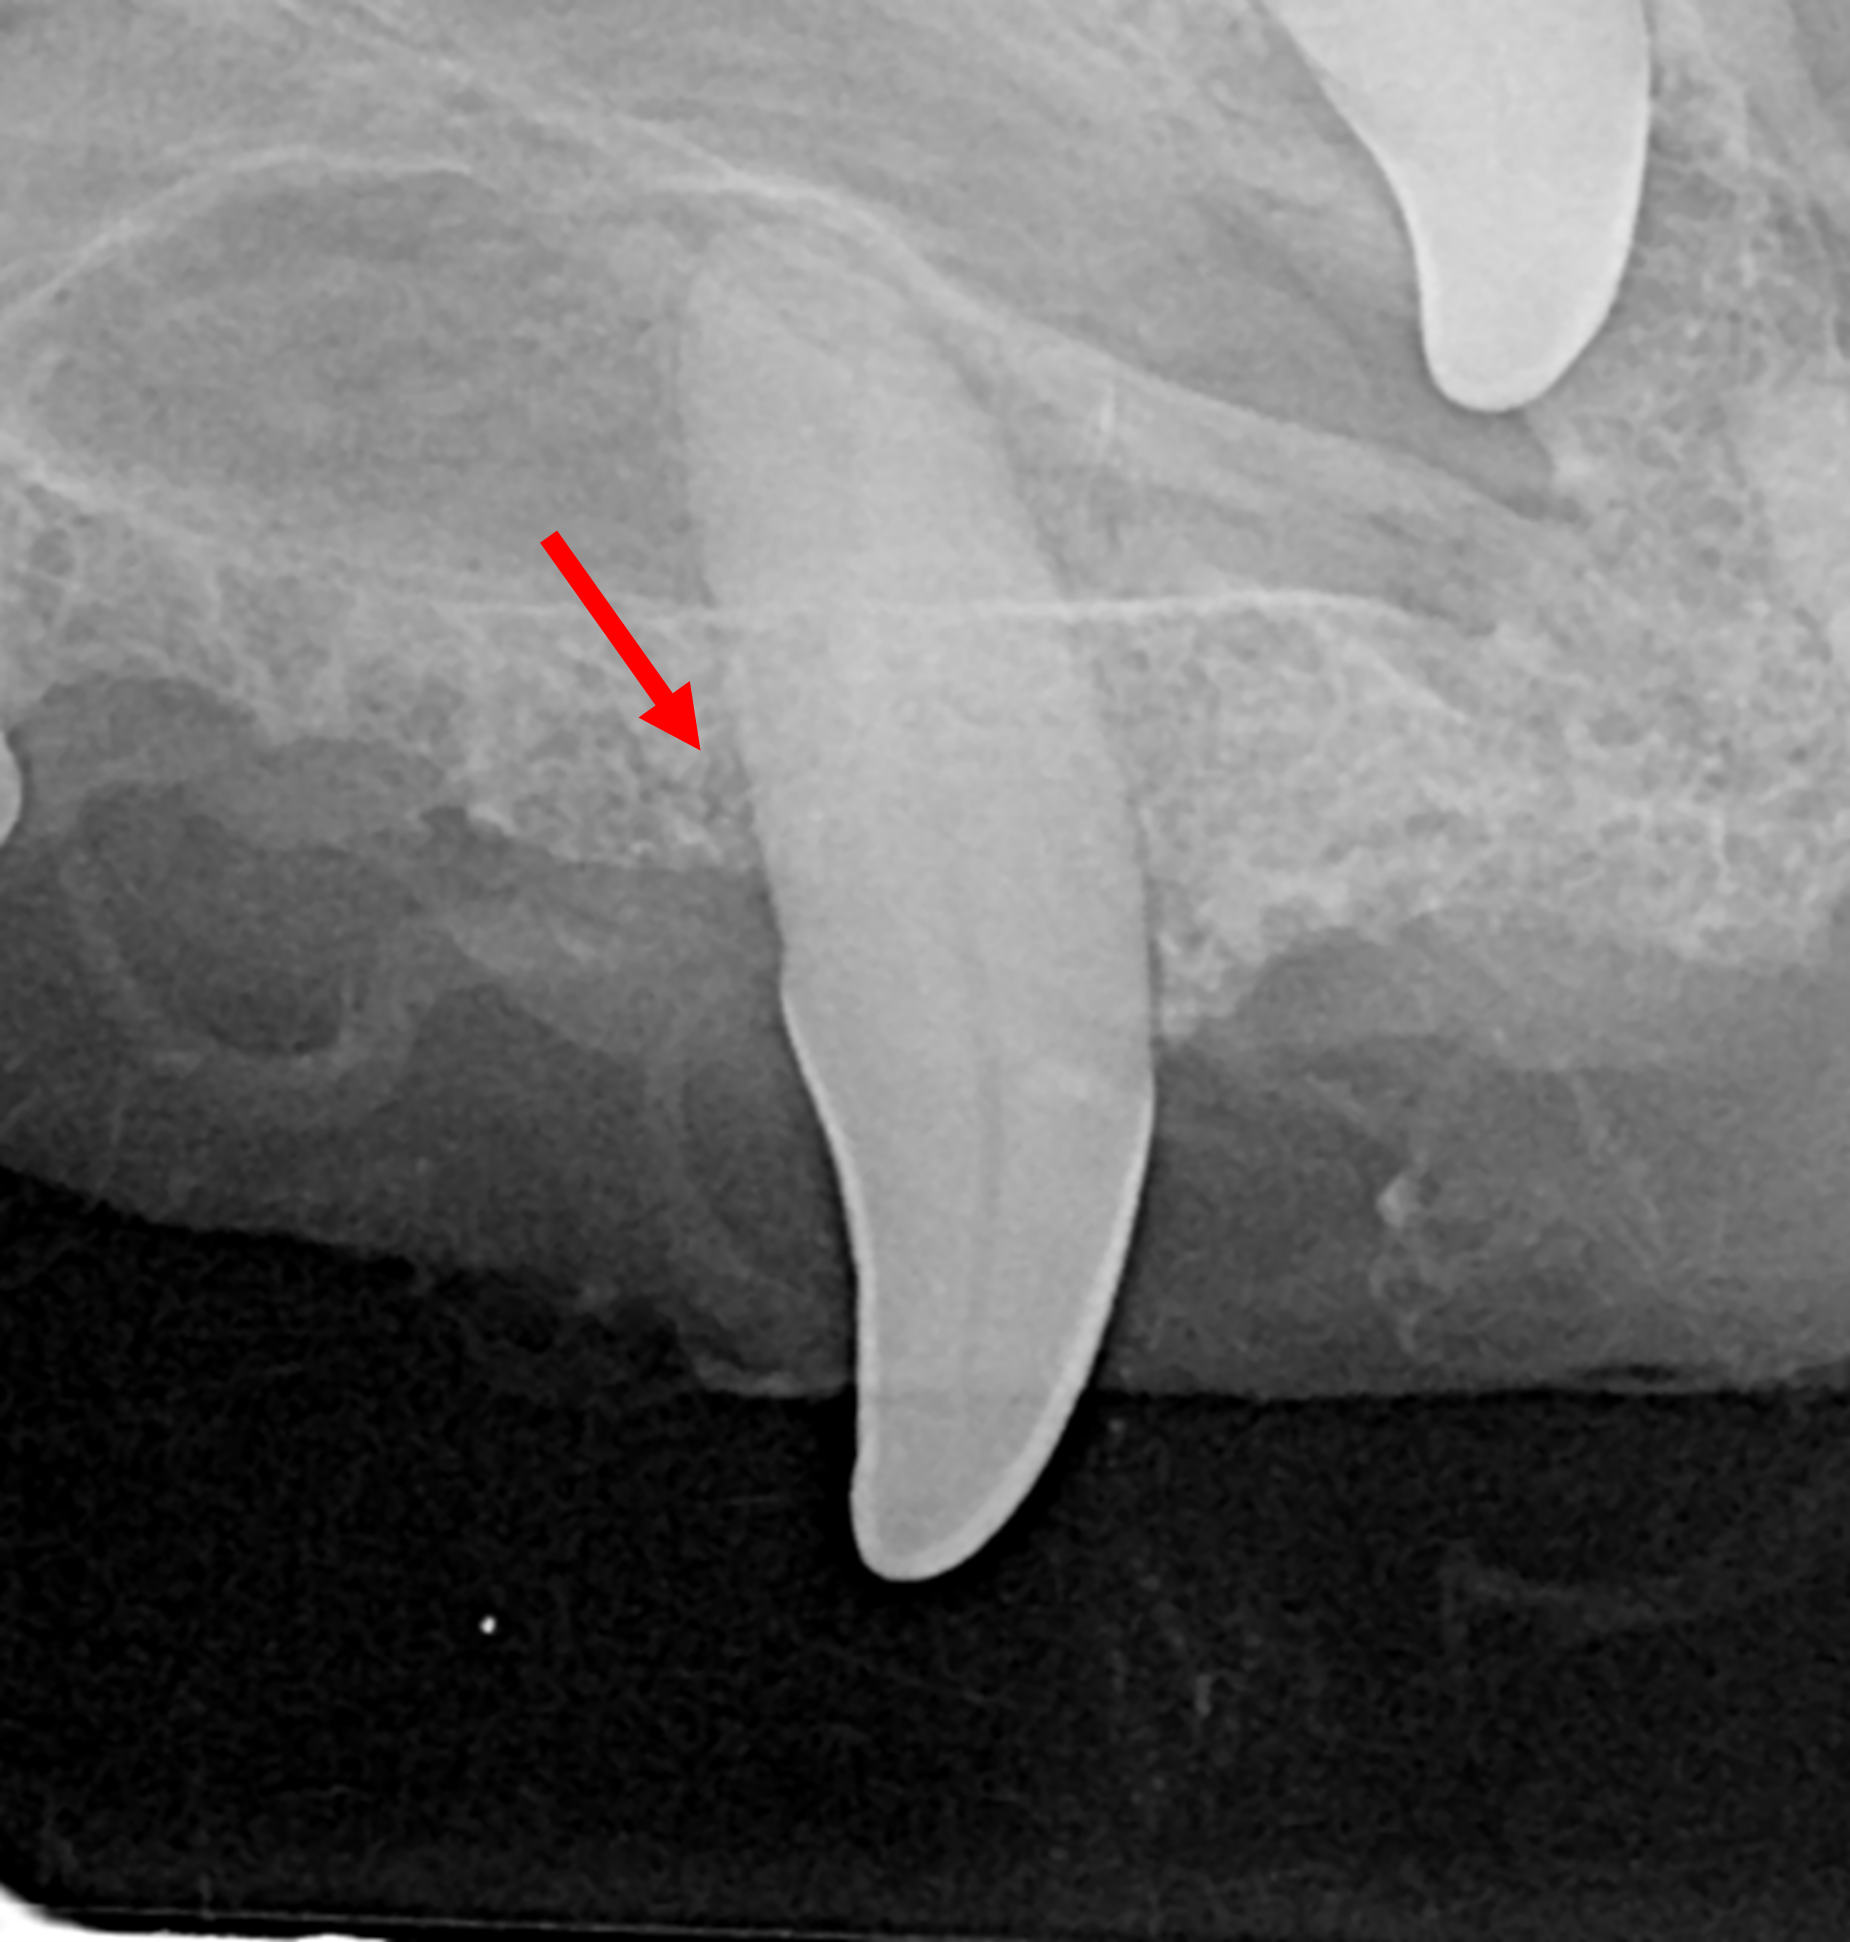

Advanced periodontal treatment is aimed at maintaining important teeth long term when they have certain types of periodontal disease.

The treatments can include bone grafting and guided tissue regeneration, as well as therapy for pocket reduction and for removal of excess gum tissue. Many of the treatments are very effective in the right pet and the right defect, but almost all will require a high-level home care following treatment. Guided tissue regeneration is not expected to succeed without daily toothbrushing. Follow-up professional care will also be required to ensure long-term success.